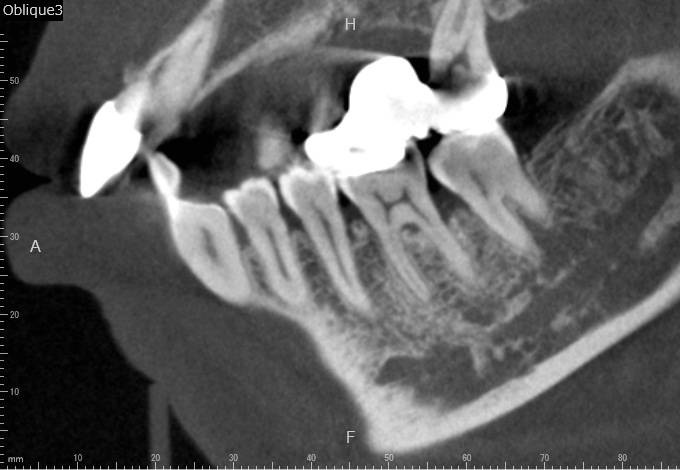

Case2

術前

術中

術後

| 治療説明 | 右下6に重度の歯周病があり、通常の歯周治療でも改善しませんでした。歯周組織再生療法を行い、吸収してしまった骨を再生し、今後の歯周病の進行リスクを減らす事ができました。歯肉退縮もあったため同時に結合組織を移植し、骨と歯肉の再生を同時に行っています。 |

| 治療回数・期間 | 6ヶ月 |

| 副作用とリスク | 手術後に出血、腫脹、疼痛が生じることがあります。手術後は術部の創傷安定のためにブラッシング制限、食事制限があります。手術が複数回となることがあります。 |

| 料金(税込) | 再生療法:165,000円 結合組織移植:55,000円 総額:220,000円 |